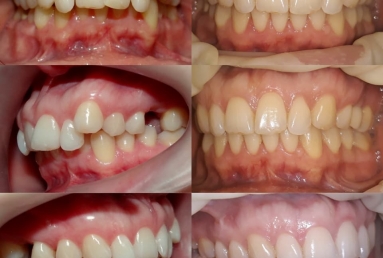

SAPPHIRE ORTHODONTIC DEVICE

Orthodontic treatment, external sinus lifting.

Orthodontic treatment, external sinus lifting, dental implant and zirconium crown.